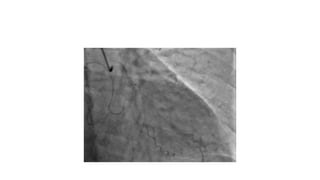

A 57-year-old woman was admitted to the hospital with chest pain. Electrocardiograms and troponin levels were normal. Intravascular ultrasound was performed before placing a stent in the left main coronary artery and left anterior descending artery to treat a blockage. The minimum lumen area increased to 4.24mm x 4.13mm after stenting.